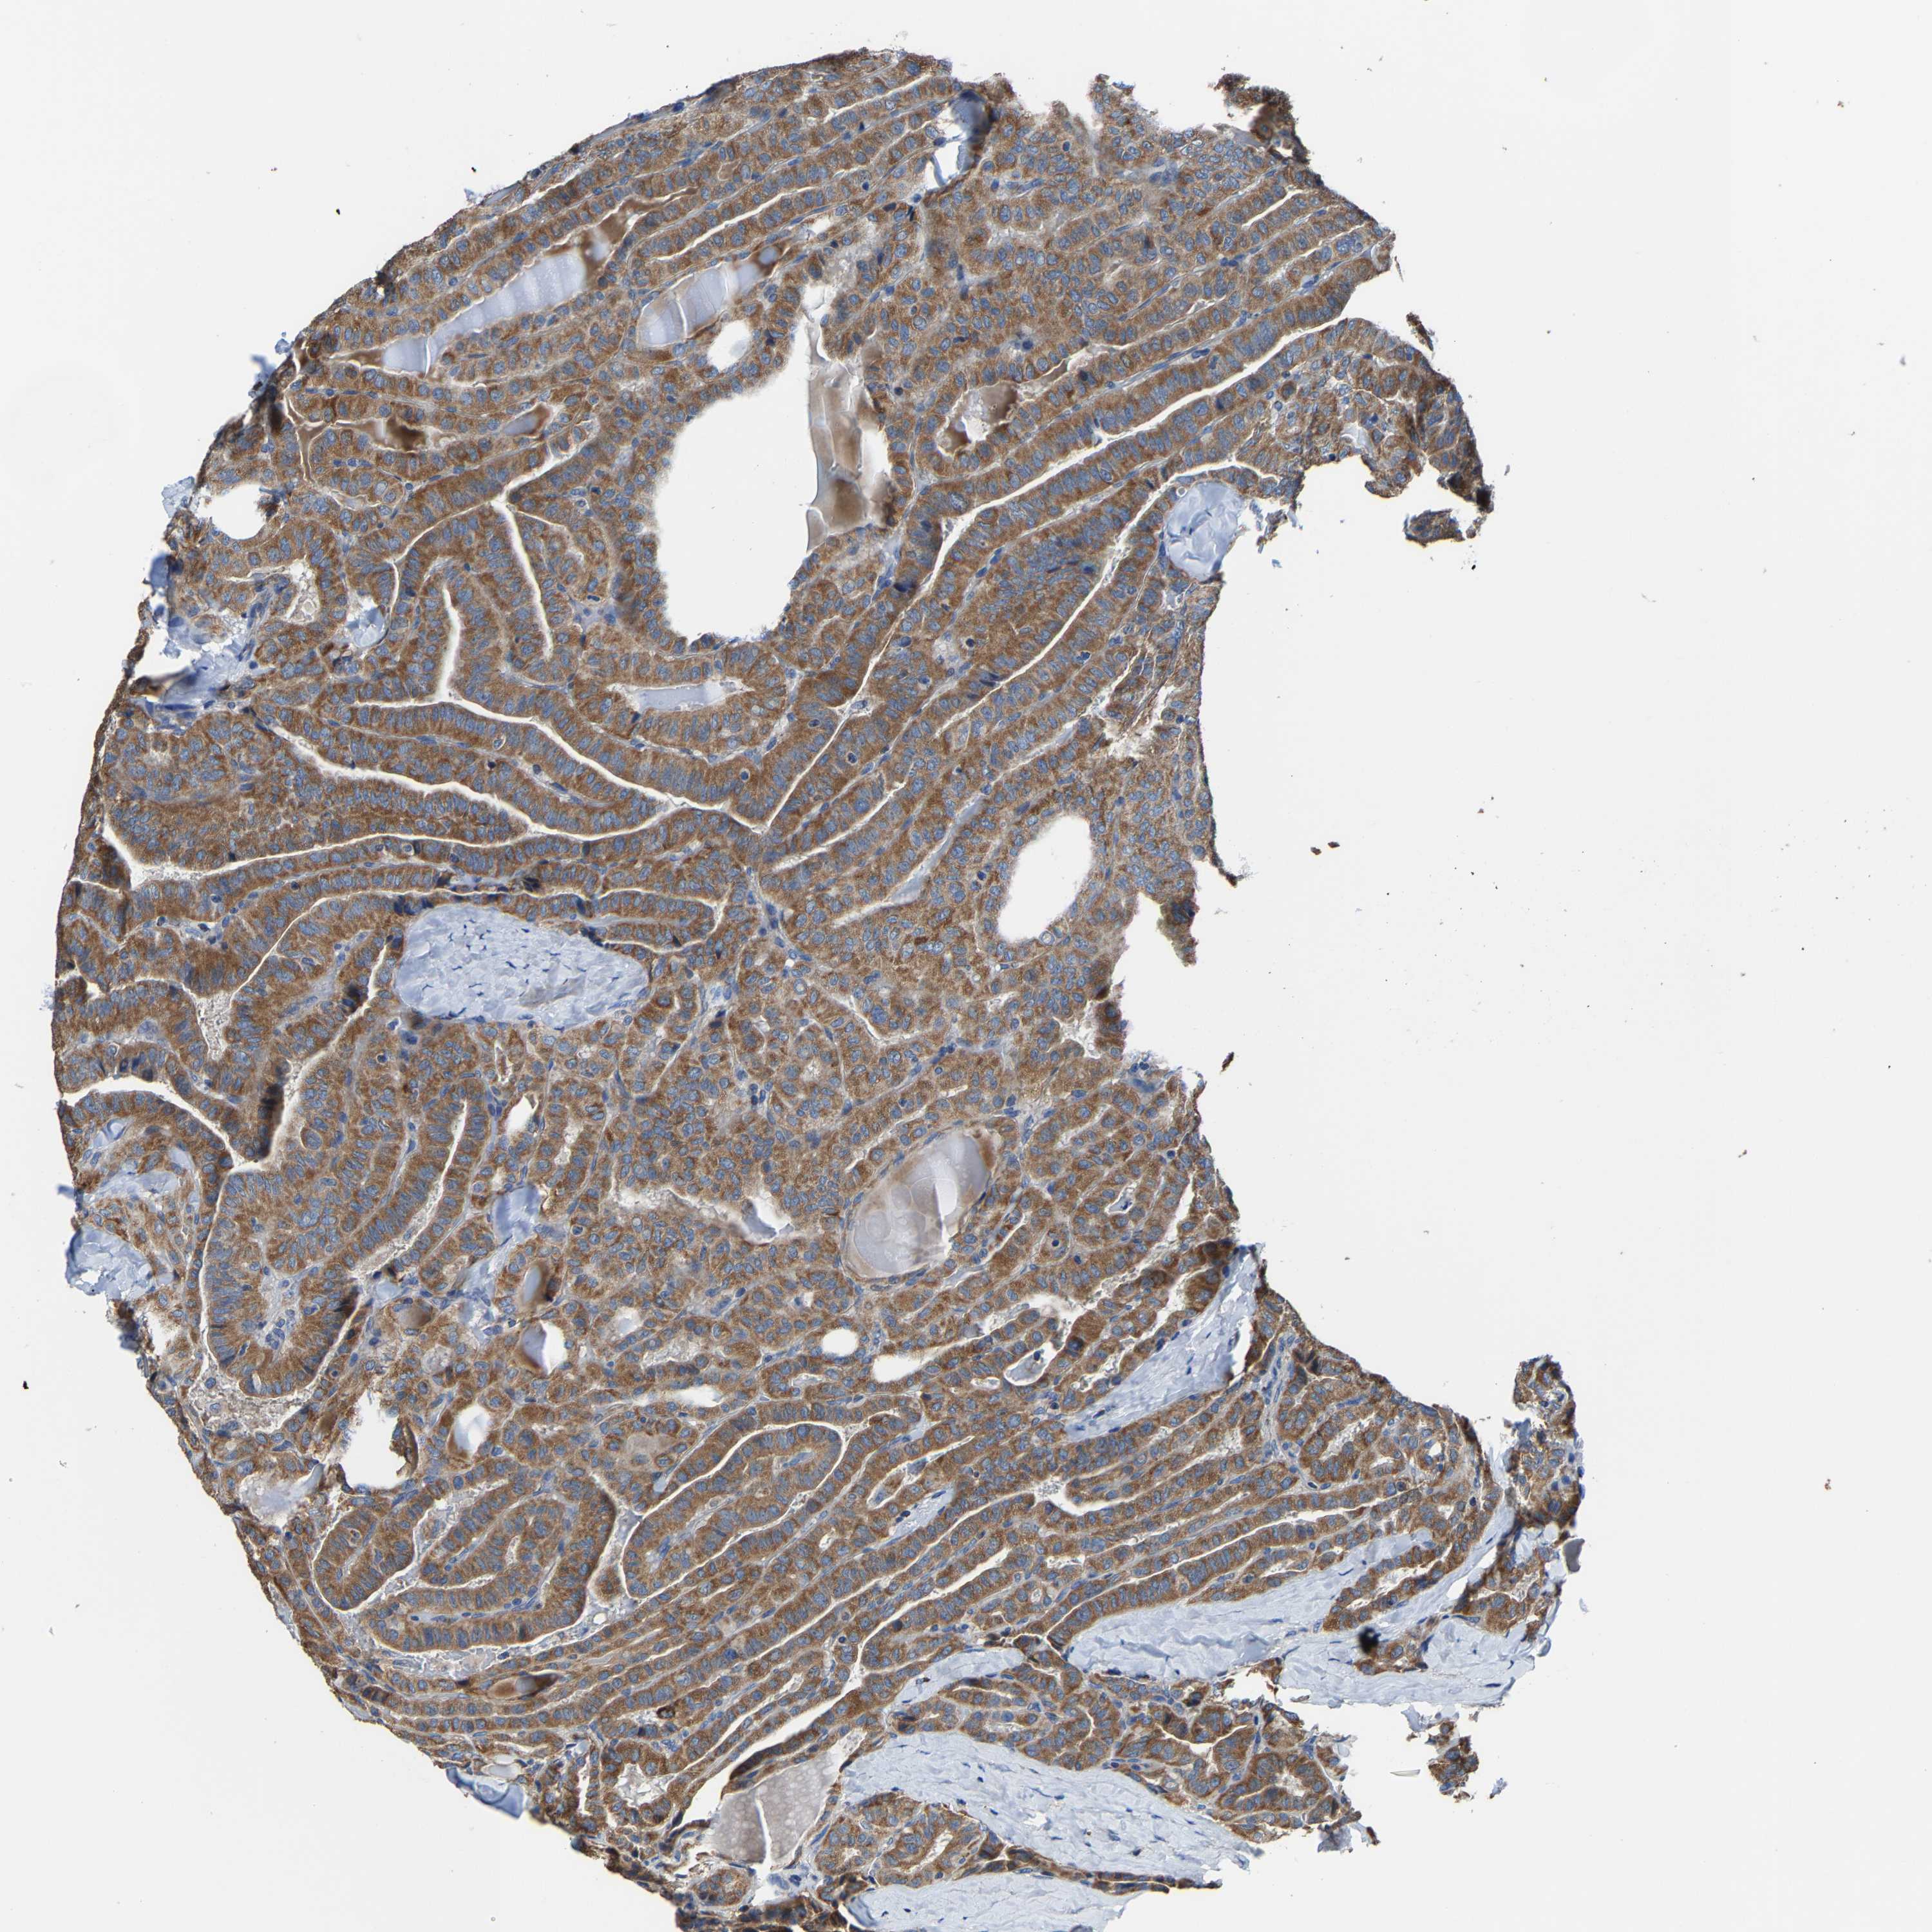

THYROID CANCER - Protein expressioni

A mouse-over function shows sample information and annotation data. Click on an image to view it in a full screen mode. Samples can be filtered based on level of antibody staining by selecting one or several of the following categories: high, medium, low and not detected. The assay and annotation is described here.

Note that samples used for immunohistochemistry by the Human Protein Atlas do not correspond to samples in the TCGA dataset.

Antibody stainingi

Antibody staining in the annotated cell types in the current human tissue is reported as not detected, low, medium, or high, based on conventional immunohistochemistry profiling in selected tissues. This score is based on the combination of the staining intensity and fraction of stained cells.

Each image is clickable and will lead to virtual microscopy that enables deeper exploration of all samples and also displays staining intensity scores, fraction scores and subcellular localization as well as patient and tissue information for each sample.

Antibody HPA020959

Antibody HPA053471

Staining

High

Medium

Low

Not detected

Intensity

Strong

Moderate

Weak

Negative

Quantity

>75%

75%-25%

<25%

None

Location

Nuclear

Cytoplasmic/membranous

Cytoplasmic/membranous,nuclear

Papillary adenocarcinoma, NOS

Follicular adenoma carcinoma, NOS